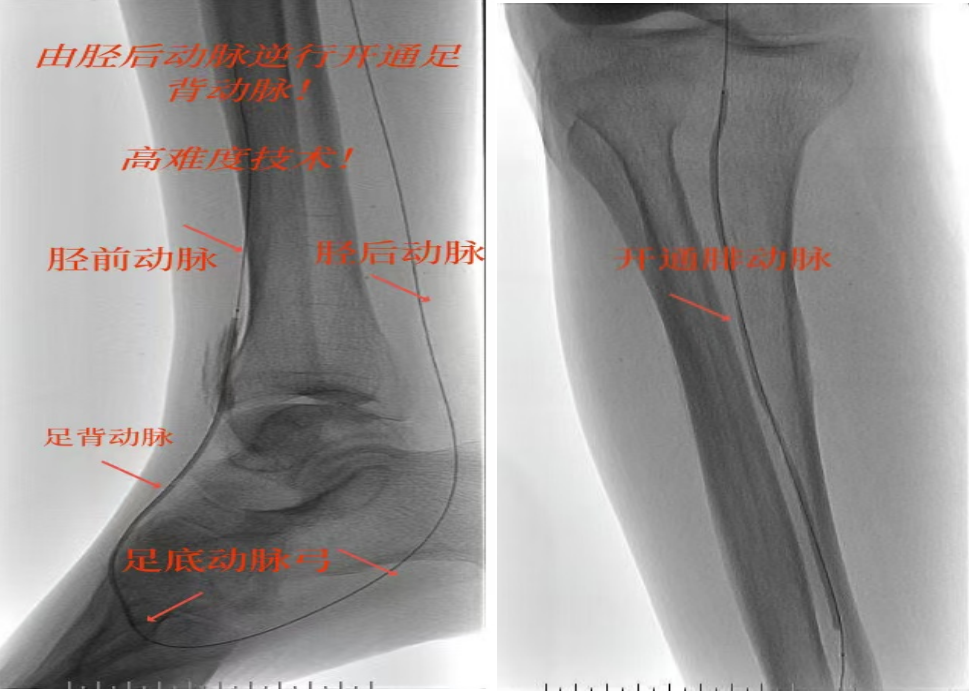

绝处逢生!“糖足”患者免截肢|市中医医院高难度介入“逆行破冰”立大功!

去疾 2025-07-03 -